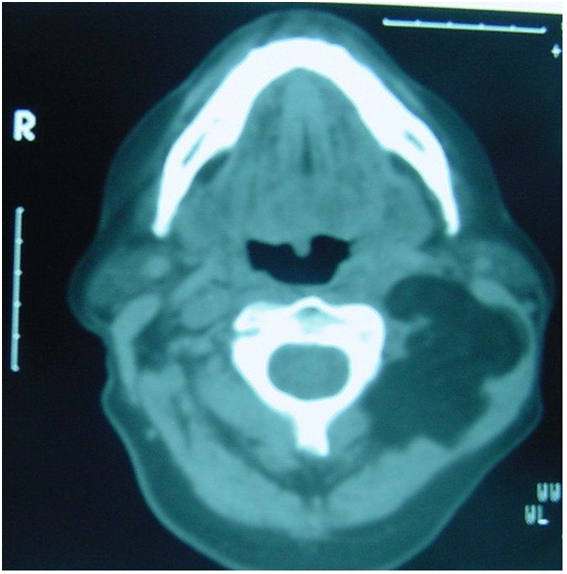

A contrast enhanced magnetic resonance imaging (MRI) scan demonstrated a well-defined homogeneous mass lesion in the left side of the neck (Figure 3). Signal characteristics were consistent with a lipoma. It appeared to have arisen in the fat space deep to the left sternomastoid muscle which was significantly enlarged. The left carotid sheath was displaced medially into the parapharyngeal space.

Figure 3 Extent of infiltrating lipoma demonstrated on contrast MRI scan (coronal cut).

In the case reported the use of CT scanning proved invaluable in the diagnosis of a lipoma at initial presentation. Greater soft tissue definition provided by contrast MRI seven years later when the patient presented with enlargement of the neck mass permitted better delineation of tumour extent. Specifically it allowed refinement of the original diagnosis to an infiltrating lipoma of the neck.